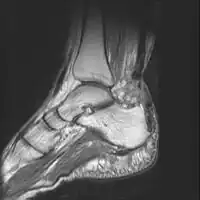

Imaging

Musculoskeletal ultrasonography can be used to determine the tendon thickness, character, and presence of a tear. It works by sending extremely high frequencies of sound through the body. Some of these sounds are reflected back off the spaces between interstitial fluid and soft tissue or bone. These reflected images can be analyzed and computed into an image. These images are captured in real time and can be very helpful in detecting movement of the tendon and visualising possible injuries or tears. This device makes it very easy to spot structural damages to soft tissues, and consistent method of detecting this type of injury. This imaging modality is inexpensive, involves no ionizing radiation and, in the hands of skilled ultrasonographers, may be very reliable.

MRI can be used to discern incomplete ruptures from degeneration of the Achilles tendon, and MRI can also distinguish between paratenonitis, tendinosis, and bursitis. This technique uses a strong uniform magnetic field to align millions of protons running through the body. These protons are then bombarded with radio waves that knock some of them out of alignment. When these protons return they emit their own unique radio waves that can be analysed by a computer in 3D to create sharp cross sectional image of the area of interest. MRI can provide unparalleled contrast in soft tissue for an extremely high quality photograph making it easy for technicians to spot tears and other injuries.